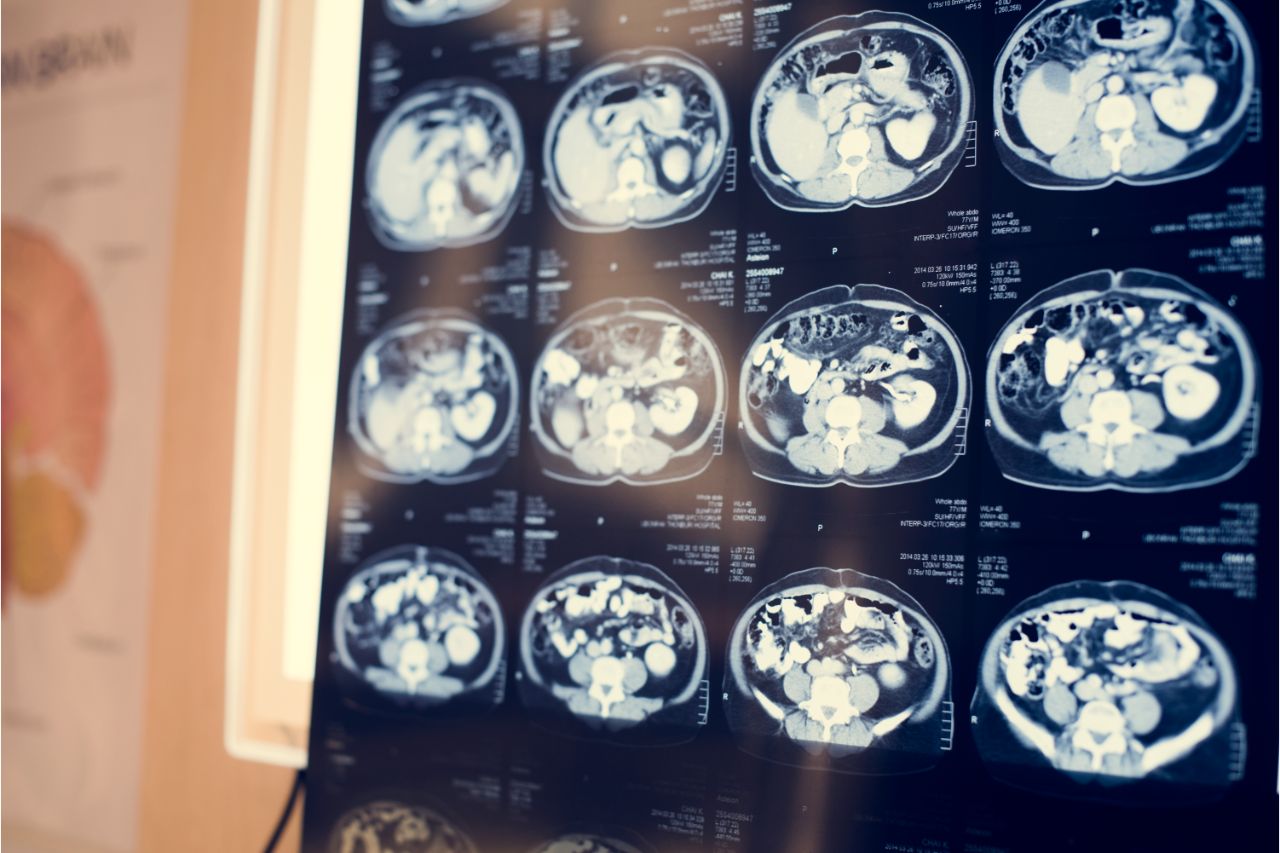

Imaging tests and an electroencephalogram at a Las Pinas medical center can reveal tumors and other abnormalities that can cause seizures. This disorder can affect all races and ages, which is why it pays to know its causes. Continue reading to learn more about these.